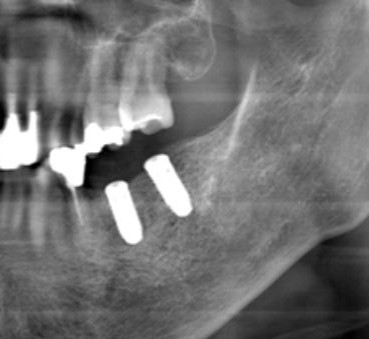

歯科用CT/デジタルレントゲン

歯や顎の骨の状態を3D(立体)で撮影できる「歯科用CT」と、2D(平面)で撮影する「デジタルパノラマレントゲン」の2役を1台でこなす装置です。